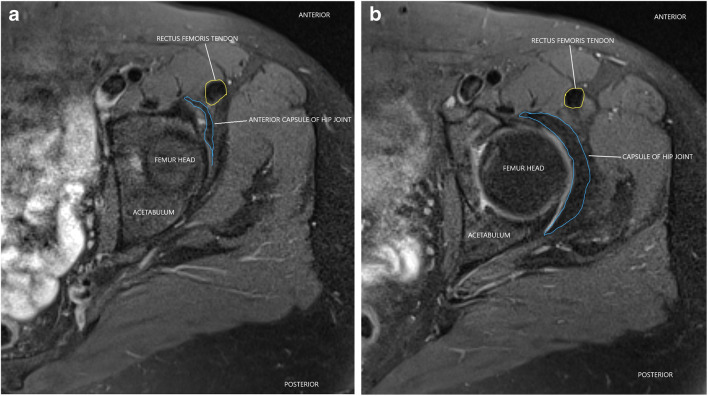

Axial T2 fat saturated MRI image of hip in a normal 47-year-old patient demonstrating preserved tissue plane between the normal anterior capsule of hip joint (outlined by blue lines) and rectus femoris tendon (outlined by yellow line) at level of superior aspect of hip joint (Fig. 3a) and at a slightly inferior (Fig. 3b) level

Fig. 4.

Post-operative pain following surgery for femoroacetabular impingement has been attributed to formation of intra-articular adhesions, extra-articular adhesions along the scope portal, repeat injury to intra-articular structures, or incomplete correction of femoroacetabular impingement bony morphology amongst other causes [4]. The intra-articular adhesions can occur between repaired portion of labrum and adjacent overlying capsule or slightly inferiorly, between femoral neck and overlying capsule. The extra-articular adhesions can occur along the arthroscopy portal tract along the anterior hip, between the external surface of joint capsule and overlying flexor tendon sheath with resultant loss of plane of separation between these structures (Figs. 2, 3, and 4).